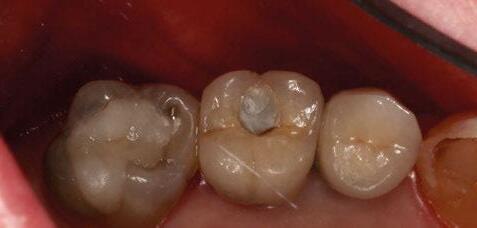

A partir del estudio radiológico y de las imágenes fotográficas podemos observar edentulismo de 17, 15, 14, 12,

Figura 1a. Foto intraoral frontal inicial.

Figura 1b. Foto intraoral lateral izquierda inicial.

Figura 1c. Foto intraoral lateral derecha inicial.

25, 26, 28, 37, 38, 47 y 48. Presentaba corona desajustada en 13 con extensión en 12, implantes en 35-36, 45-46, con coronas ferulizadas en 35-36, 45-46, y dientes anteriores superiores con enfermedad periodontal Grado IV.